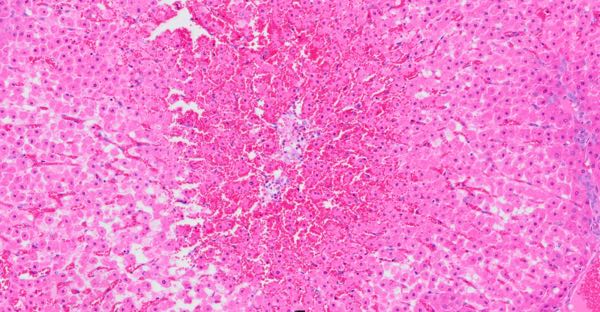

The livers of Lambs 1 and 2 with gross hepatic lesions showed marked acute periacinar and midzonal hepatocyte degeneration and necrosis with replacement haemorrhage, while the kidneys had no significant histological lesions. Lamb 3 had renal lesions of marked multifocal acute tubular degeneration and necrosis, while the liver showed only mild non-specific changes. This lamb also had pulmonary changes of multifocal alveolar oedema, congestion and mild interstitial pneumonia.

Figure 6. Liver of Lamb 1. Periacinar pattern of hepatocyte injury with replacement haemorrhage (H&E, 12.5x).

Figure 7. Liver of Lamb 1. Periacinar to midzonal necrosis and degeneration with replacement haemorrhage (H&E, 50x).